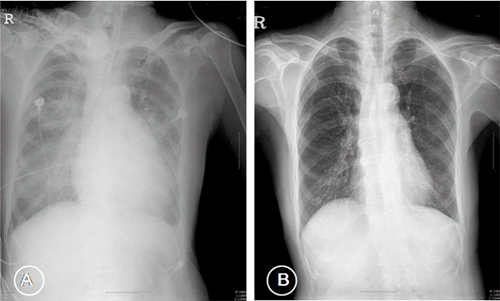

Figure 1 Chest X-ray showed cardiomegaly with pulmonary edema (A),

Previous normal chest x-ray (left) and CHF stage II with perihilar haze